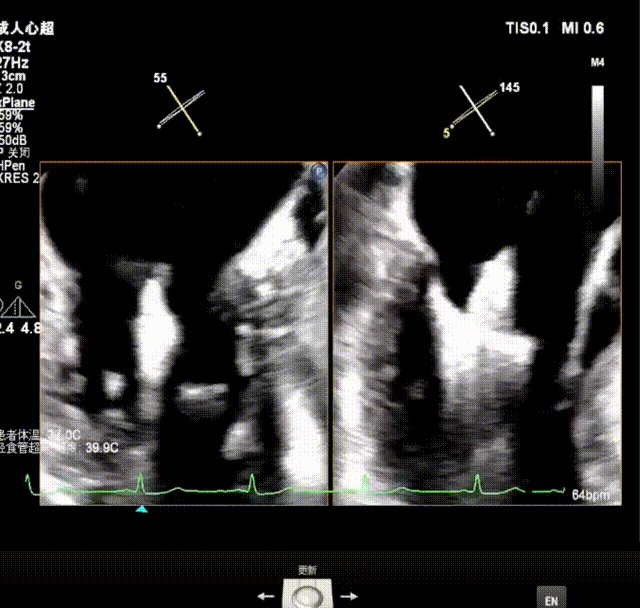

瓣上M/L和A/P调整瓣膜夹,在X-plane进行超声确认,

瓣上进行前后瓣对应夹片确认

瓣上M/L和A/P调整瓣膜夹,在X-plane和3D下反复确认弹道和夹臂方向